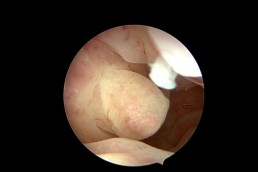

Polipii uterini reprezintă proliferări locale ale endometrului (mucoasa ce căptușește cavitatea uterină) și în marea majoritate a cazurilor sunt benigni. Ei pot provoca sângerări anormale, infertilitate sau pot interfera cu implantarea embrionilor în cursul fertilizării in vitro. Polipii endometriali pot fi diagnosticați cu ajutorul ecografiei, iar histeroscopia certifică acest diagnostic. În plus, histeroscopia permite și rezecția și extragerea polipilor endometriali. (fig. 3, 4)